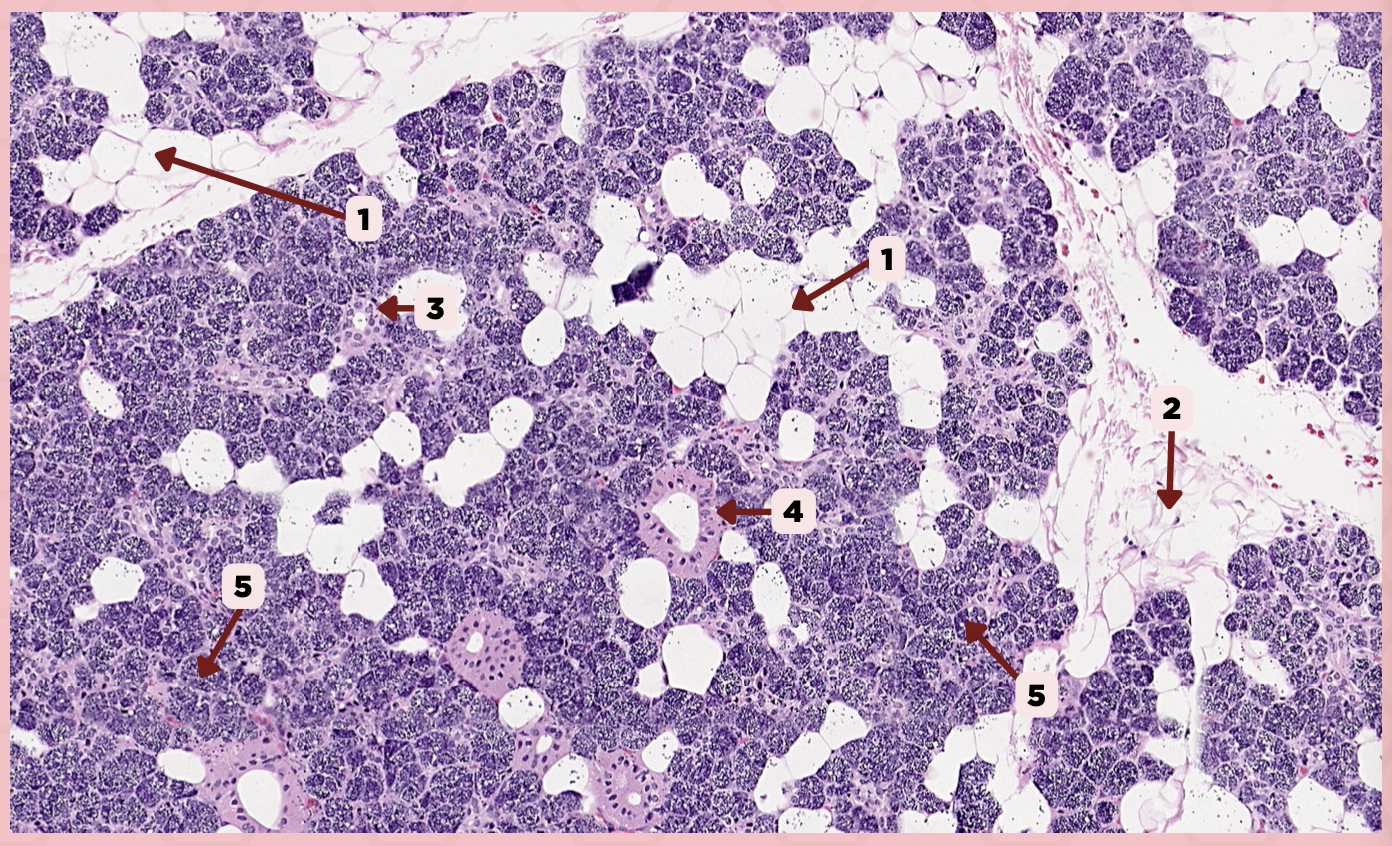

A) Myoepithelial Cells

These cells are associated with secretory units of salivary glands that are contractile to help in ejecting secretions

A) Myoepithelial Cells

B) Goblet Cells

C) Adipocytes

A) Striated Ducts

This duct has a wall consisting of a simple cuboidal or columnar epithelium and is formed by the union of intercalated ducts.

A) Striated Ducts

B) Interlobular Ducts

C) Intercalated Ducts

Parotid

Identify the specimen.

Secretory Acini

Identify the structure labeled as 1.

Myoepithelial Cell

Identify the structure labeled as 2.

Secretory Duct

Identify the structure labeled as 3.